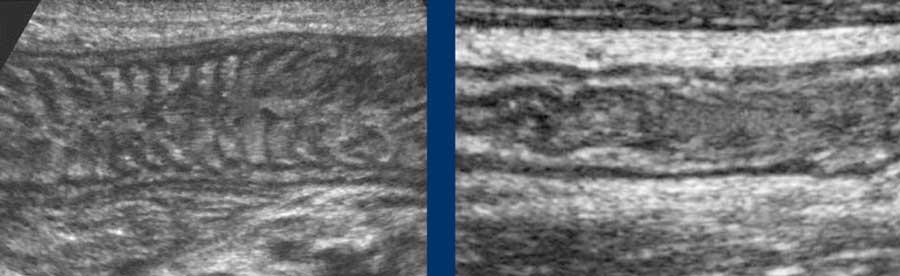

Normal small bowel in the longitudinal plane.

Jejunum

Hỗng tràng (hình bên trái) chủ yếu nằm ở góc phần tư trên trái, và chứa nhiều nếp van Kerckring (van hồi manh tràng) hơn so với hồi tràng (hình bên phải), vốn nằm nhiều hơn ở góc phần tư dưới phải.

Đo độ dày thành ruột bằng siêu âm là khó khăn vì độ dày thay đổi theo các chuyển động nhu động ruột.

Ở cá nhân này, các số đo trong mặt phẳng dọc (hình trên) và trong mặt phẳng ngang khi ép nhẹ (hình dưới bên trái) có sự biến thiên đáng kể, nhưng khi ép vừa phải (hình dưới bên phải) các số đo có độ tái lập tốt và chính xác.

Vì lớp thanh mạc tăng âm mỏng hiếm khi có thể nhìn thấy rõ, độ dày thành ruột được đo từ bờ ngoài của lớp cơ mặt bụng đến bờ ngoài của lớp cơ mặt lưng, và sau đó tất nhiên, chia đôi.

Thông thường, độ dày thành ruột non đơn lớp khi ép là khoảng 1,5 – 2,5 mm.

Đo độ dày thành ruột bằng siêu âm theo cách này có tính tái lập và tương đương với những gì các phẫu thuật viên thực hiện bằng ngón tay trong quá trình mở bụng để xác định xem ruột non có bất thường hay không.